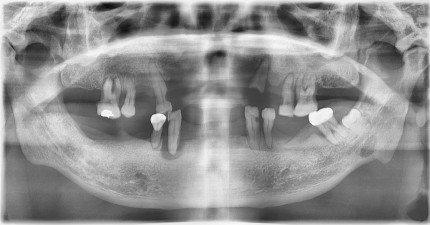

쿨쿨플란트치과 전악임플란트 치료 전후사진